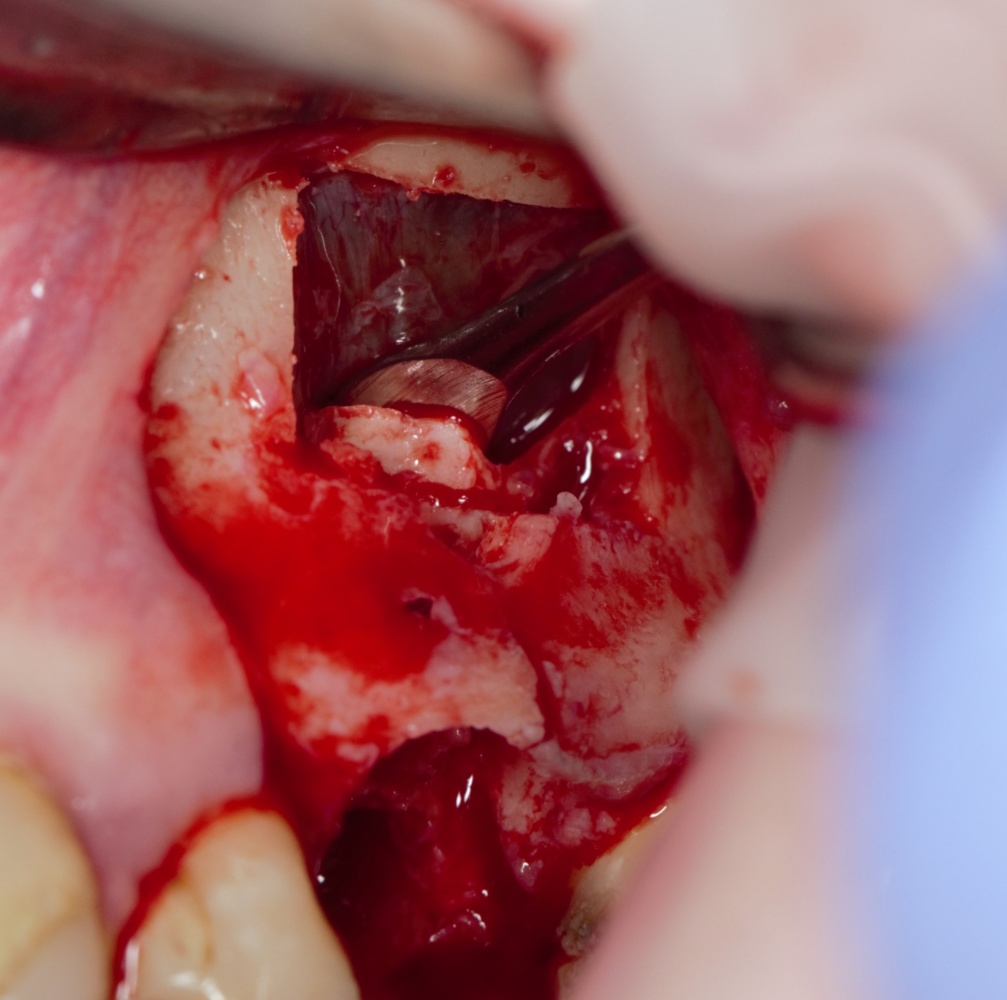

Я зафиксировал костный блок практически без адаптации на несколько винтов. Обрати внимание, что винты находятся в зоне, где не планируется установка имплантатов. Фиксация должна быть надежной, поскольку мне еще предстояла подготовка лунок для имплантатов. Трех винтов для этого вполне достаточно.

Дальнейшая адаптация костного блока свелась к сглаживанию острых краев. После чего я приступил к подготовке лунок и установке имплантатов.

Установка имплантатов.

Напомню, что для этой работы я выбрал субкрестальные имплантаты Ankylos C/X. Они прекрасно сочетаются с любым методом остеопластики.

Я не планирую установку супраструктур или коронок, поэтому на уровень первичной стабильности можно положить болт. Даже наоборот — чем меньше крутящий момент при установке, тем лучше. Для имплантатов Ankylos и подобных им, это особенно важно. В общем, момент силы при установке — не более 10-15 Нсм.

Ремарка: имплантаты с предустановленными имплантодержателями хороши тем, что с ними легко контролировать позиционирование имплантатов. В случае с Ankylos С/Х - еще и крутящий момент. Имплантодержатель должен отсоединяться от имплантата с легким щелчком. Если его клинит, и тебе приходится прикладывать для этого усилия, то ты, однозначно, превысил момент силы во время установки имплантата. Следовательно, жди проблем.

Глянем на то, что получилось:

Осталось адаптировать костный блок (убрать острые края), проверить его фиксацию и, при необходимости, добавить винты. Десятисекундное дело.